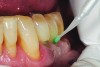

Fig 7. Cavities were cleaned with 20% polyacrylic acid solution.

The case demonstrated in Figure 6 through Figure 11 shows the ease with which non-carious Class V lesions can be handled with bulk-filled GIC restorations. Several cervical lesions (abfractions) of significant depth in permanent posterior teeth showed signs of turning carious (Figure 6). The author elected to restore them with the EQUIA technique. For non-carious lesions it is only necessary to freshen the cavity surface and margins with a diamond or carbide bur and to remove any visibly damaged hard tissue. It is then most ideal to remove any smear layer by treating the cavities with a weak acidic solution such as 20% polyacrylic acid (Figure 7). It is important that the clinician not substitute this acidic solution with a conventional phosphoric acid solution or gel used for etching tooth structure prior to resin bonding, as using the conventional solution will remove important mineral content that the GIC requires to bond with chemically. Once the cavities were isolated, a high-viscosity auto-curing GIC was mixed and syringed into the cleaned cavities with a bulk-fill technique (Figure 8). A plastic instrument was then used to condense and shape the material to the cavity walls and margins. The GIC will set in approximately 2:30 seconds to a sufficient level where it is safe to begin adjusting and finishing with rotary instruments. After the restorations were finished, they were coated with a nanofilled, light-cured resin glaze (Figure 9 and Figure 10). The glaze protects the surface of the GIC while it sets completely and enhances the physical strength of the final restoration. The completed GIC restorations (Figure 11) showed excellent esthetics comparable to composite resin.